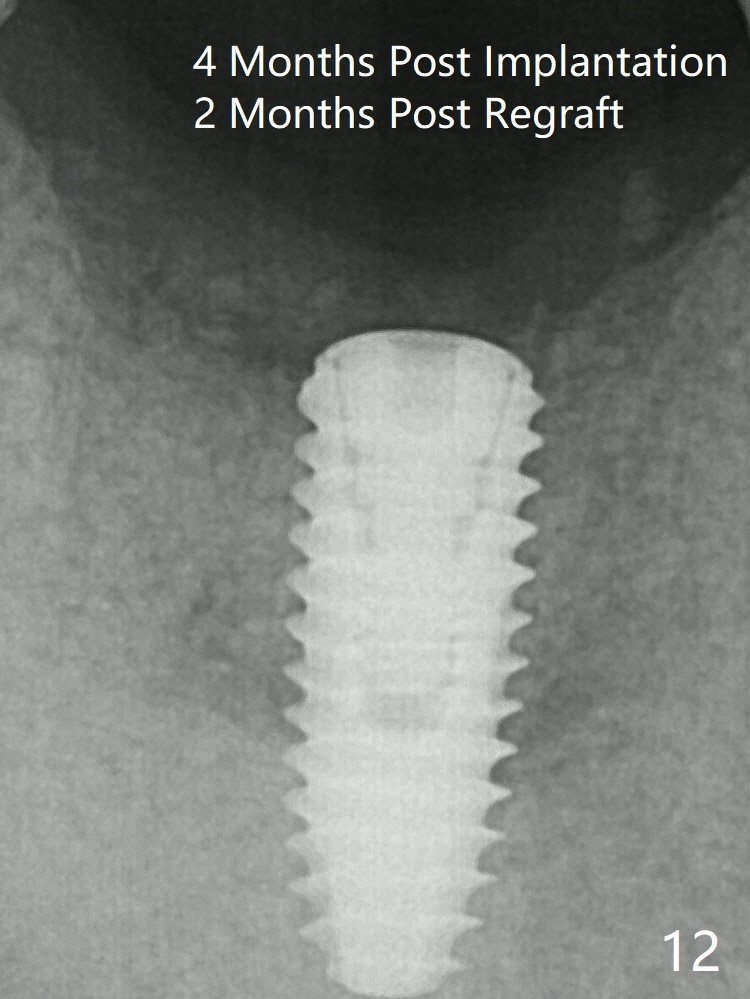

Mixture of cortical bone (125μm – 850μm) and cortical/cancellous bone (.5-1 mm) with PRF (sticky bone, B in Fig.6). There is not enough bone coronal to the implant plateau 2 months post graft (Fig.12). Three months later, bone graft will be re-placed possibly with uncover.